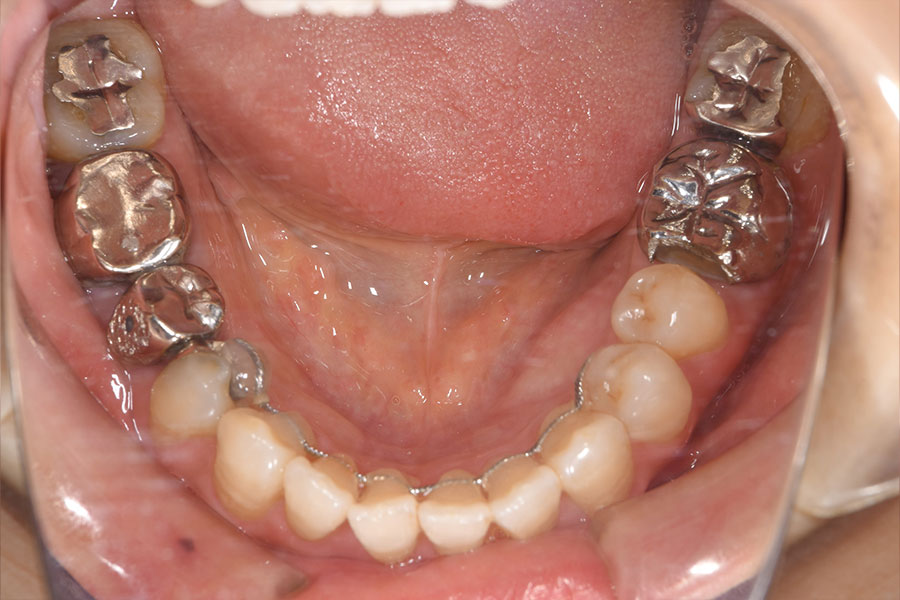

After -下顎-